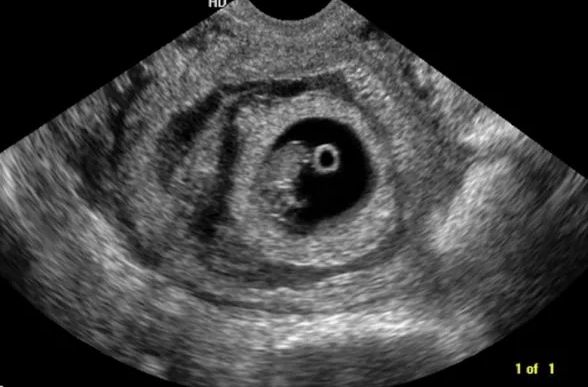

Связь между ретрохориальной гематомой в первом триместре и исходами одноплодной беременности после ЭКО. Обзор и метаанализ.

Точная патофизиология ретрохориальной гематомой (РХГ) остается неизвестной , но , предполагается ,что имеет место нарушение ангиогенеза. Частота распространения точно неизвестна , но, в зависимости от используемых критериев постановки диагноза может достигать от 2 до 40 %. Есть факторы риска ,которые могут повлиять на увеличение частоты РХГ (многоплодная беременность , криоперенос, пороки развития матки, инфекции, привычный выкидыш). Цели исследования: - оценка связь между РХГ в первом триместре (≤ 12 недель беременности) и материнскими и неонатальными исходами у женщин, зачавших с помощью вспомогательных репродуктивных технологий (ВРТ). - результаты могут предоставить важную информацию для медицинского